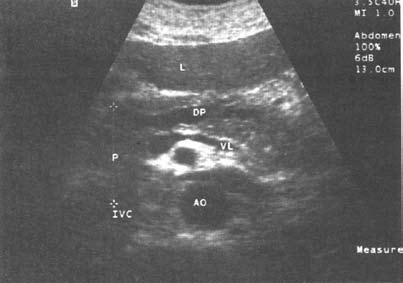

Ультразвуковое исследование (сканирование) является одним из наиболее информативных и притом неинвазивных методов исследования ПЖ и должно осуществляться во всех случаях, когда подозревается ее патология (рис. 137–139).

Датчик располагается в эпигастральной области и его перемещают соответственно проекции железы на области левого и правого подреберий. В норме ПЖ имеет ровные, четкие контуры и гомогенную структуру, а диаметр главного панкреатического протока не превышает 1,5–2 мм. При патологии может выявляться общее увеличение размеров органа с равномерным уменьшением эхоплотности, свидетельствующее об отеке. Уменьшение размеров железы, неоднородность структуры, наличие мелких участков уплотнения ткани, а также нечеткость контуров могут говорить о фиброзных изменениях в железе, а небольшие резко выраженные эхоположительные узелки – об очаговом обызвествлении паренхимы. Эхоструктуры высокой плотности, расположенные в протоке и дающие феномен "ультразвуковой дорожки", являются признаком внутрипротоковых конкрементов. Жидкостные образования (ложные кисты, вялотекущие абсцессы) представляются на эхограмме округлыми участками значительно пониженной эхоплотности с более или менее четкими контурами и дорсальным усилением. Хорошо сформированные ложные кисты с жидким содержимым имеют округлую или овальную форму, гомогенны и окружены четко выраженной капсулой. Содержимое несформировавшихся кист и абсцессов может быть неоднородным из-за наличия в них, помимо жидкости, тканевых секвестров и детрита.